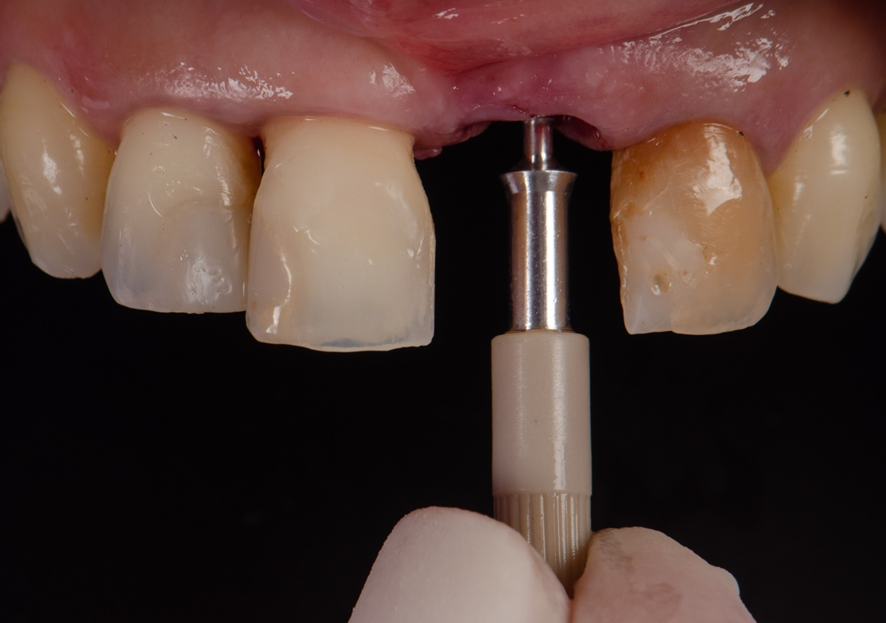

Após o implante instalado, a guia é então removida, e um SmartPeg é fixado sobre a plataforma do implante.

O Osstell é então posicionado sobre o SmartPeg, e os valores de ISQ foram obtidos atraves da RFA, sendo 64 no sentido Vestibulo-Palatino e 65 no sentido Mesio-distal. Isso fez com que optássemos por um cicatrizador personallizado, potencializando assim, um resultado mais previsível.